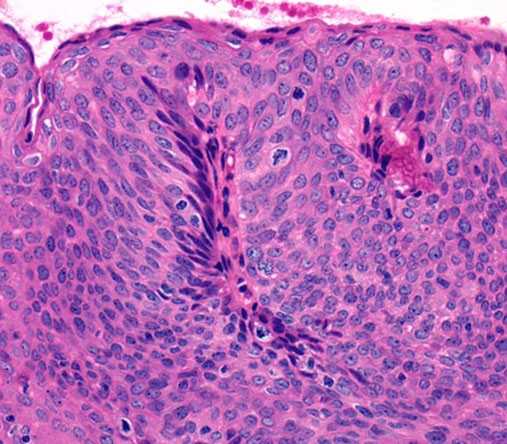

Mucosal prolapse polyps. A, Inflammatory (cloacogenic) polyp of the anorectal transition zone. B, Strands of thickened and splayed muscularis mucosae extend around the crypt bases and into the overlying lamina propria. The crypts assume an angulated and distorted appearance. C, When embedded tangentially, prolapse polyps show strands of smooth muscle that appear to encircle colonic crypts, which frequently assume a “diamond” shape. D, On the surface, mucosal prolapse polyps often contain markedly regenerative, serrated/hyperplastic-appearing epithelium and ischemic-type changes with erosion. [2]